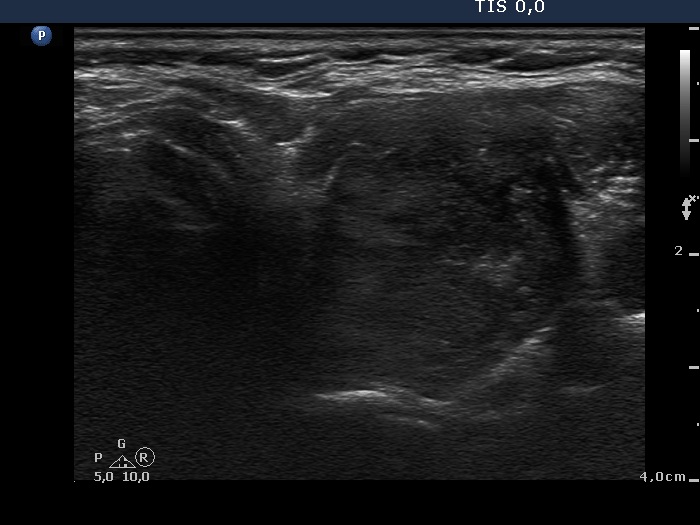

First examination (first and second rows of images):

Clinical presentation: A 41-year-old woman was referred for an evaluation of complaints suggesting hyperthyroidism.

Palpation: Both lobes were enlarged and moderately firm.

Results of blood tests: hyperthyroidism (TSH undetectable, FT4 51.8 pM/L).

Ultrasonography. A diffusely hypoechogenic thyroid was found with multiple lesions. There was a hypoechogenic lesion in the dorsal part of the right lobe. This lesion showed taller-than-wide and longer-than-wide shape. The left lobe had two lesions which were more echogenic than the non-nodular part of the lobe, however less echogenic than a normal, healthy thyroid.

Cytology was performed from the hypoechogenic nodule found in the right thyroid and from one of the hyperechogenic nodules in the left lobe. Cytological diagnosis: benign pattern corresponding to hyperthyroidism.

TSAb was elevated 11.0 U/mL (normal value below 1.5) while scintigraphy excluded the possibility of autonomy.

Thyrostatic therapy was started. We told the patient that the final solution could be surgery.